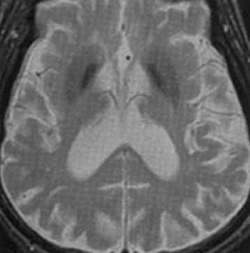

![]() IRM cérébrale - séquence T2 - Maladie de Parkinson idiopathique - hypo-intensités de la substance noire |

L'IRM sert surtout à écarter des diagnostics différentiels potentiellement accessibles à un traitement étiologique (tumeurs, parkinsonnisme vasculaire, hydrocéphalie, calcifications des noyaux de la base et diverses anomalies métaboliques,...). Dans le cadre d'une maladie de Parkinson idiopathique ont pourra cependant rencontrer les anomalies suivantes (peu sensible, peu spécifique) :

- atrophie diffuse et élargissement ventriculaire ventriculaire

- hypo-intensités des noyaux de la base et de la substance noire en FLAIR/ T2